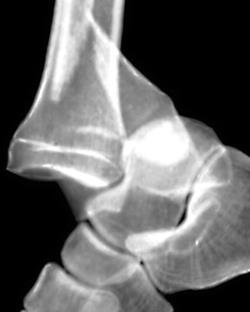

(Слева) При рентгенографии голеностопного сустава в передне-задней проекции определяется латеральный вывих подтаранного сустава. Латеральное смещение пяточной кости указывает либо на ее вывих, либо на ее перелом. Чтобы отличить вывих от перелома, необходимо выполнить рентгенографию еще и в боковой проекции.

(Справа) У этого же пациента при рентгенографии голеностопного сустава в боковой проекции подтверждается наличие вывиха подтаранного сустава. Задняя суставная поверхность пяточной кости не сочленяется с соответствующей суставной поверхностью таранной кости. Кроме того, выявляется перелом латерального отростка таранной кости. Суставные поверхности таранно-ладьевидного сустава конгруэнтны. (Слева) При рентгенографии голеностопного сустава в передне-задней проекции определяется медиальный вывих подтаранного сустава. Задняя суставная поверхность таранной кости не сочленяется с соответствующей суставной поверхностью пяточной кости.